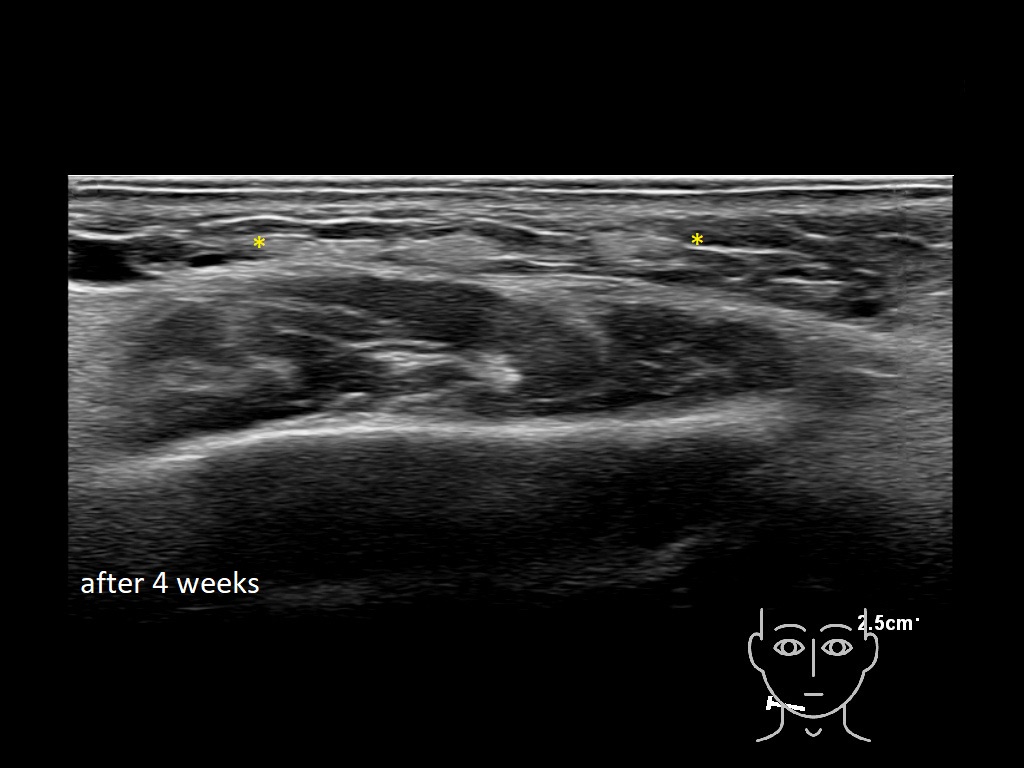

Draw in the image on the right where the fillers are located. To check if your answer is correct, please click on the secondary image.

Draw in the second image below where the fillers are located. To check if your answer is correct, swipe the first image to the right.